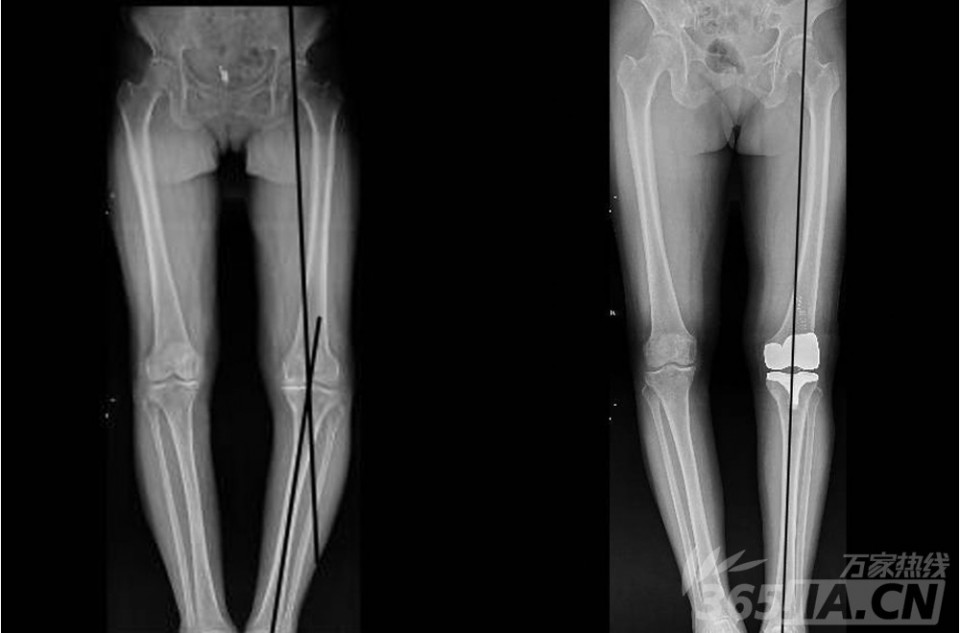

图为唐大妈计算机导航辅助下人工膝关节置换术前后对比图,术前患者力线有15°,术后为0°,基本恢复正常。(左图为手术前,右图为手术后)。据悉,该项手术从去年10月份开展以来,病人术后恢复均良好。尤为值得一提的是,膝关节置换术已纳入医保按病种收费,新农合病人在省内医院报销可达到70%。原本需要5万的手术费,报销后只需自费1.5万。